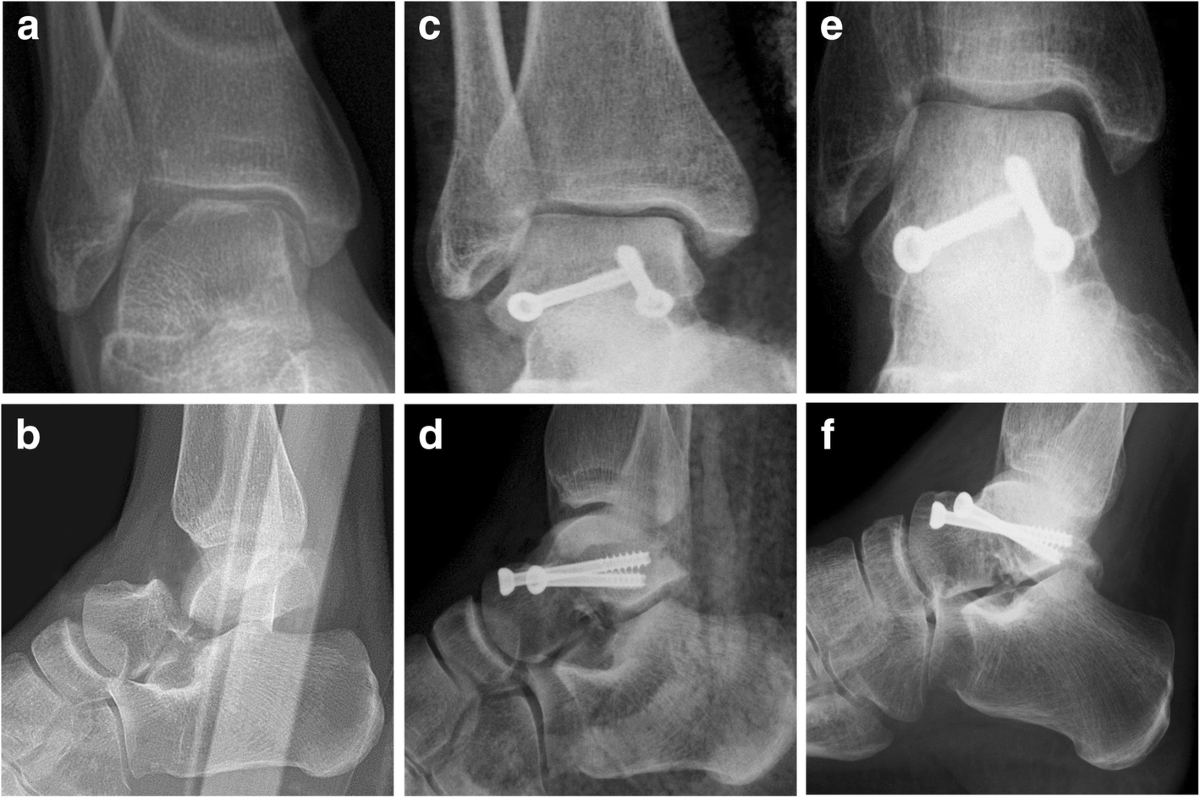

Talus fracture (95) 사진

Talus fracture approach (95) 사진